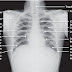

A 22 Year old patient presents with community acquired pneumonia and was reported to have allergy to penicillin. How would you approach this patient?